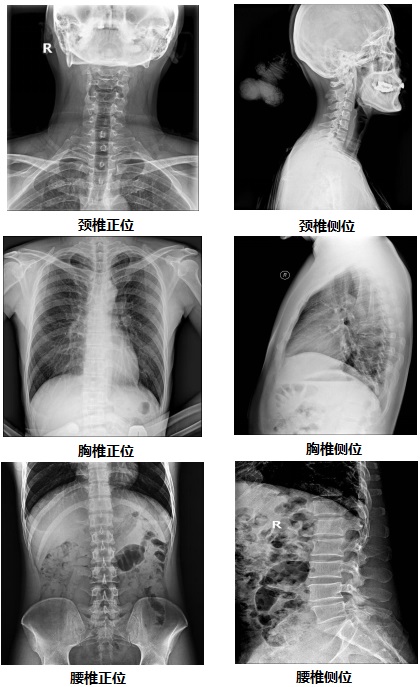

【雙板懸吊式dr機(jī)PLD7700D部分臨床效果圖】